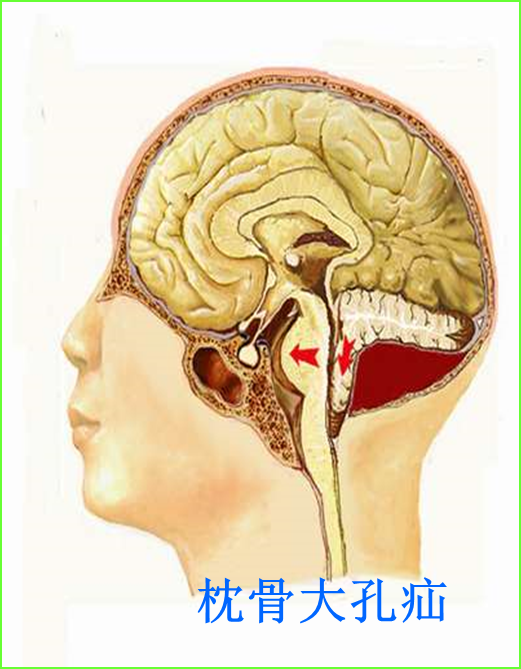

枕骨大孔疝位置图片

②枕骨大孔疝(transforamen magna herniation),为小脑扁桃体及延髓经

当小脑扁桃体疝入枕骨大孔时,阻塞了脑嵴液的循环,并且可能压迫脑干和

枕骨大孔疝可以压迫脑干的生命中枢,直接引起患者的死亡,情况非常危及